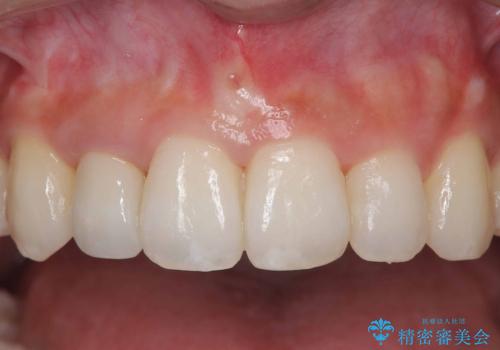

- 「前歯の見た目が気になる」を主訴に来院された患者様です。

オールセラミッククラウンで治療を行いました。

被せ物と歯の境の位置が歯肉の上に設定されており、それによって審美障害が起きていました。

歯と被せ物の境を歯肉縁下0.5㎜に設定して形成を行いオールセラミッククラウン(スペシャル)で治療を行いました。